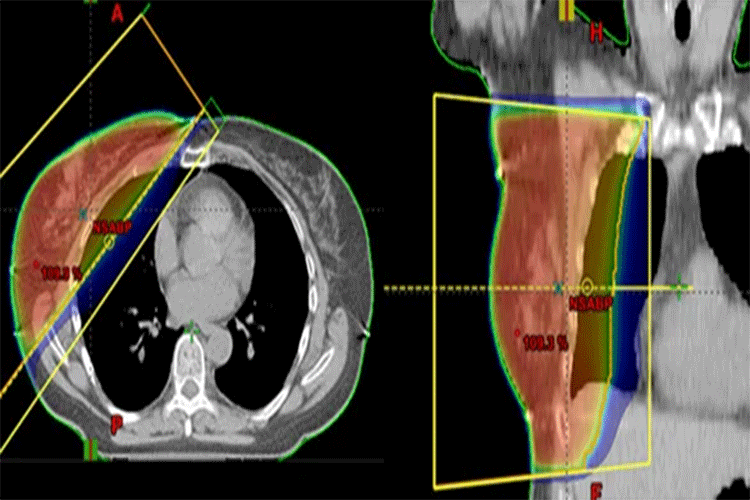

3DCRT Τρισδιάστατη Σύμμορφη Ακτινοθεραπεία (3DCRT- Three Dimensional Conformal Radiation Therapy)

Η Τρισδιάστατη Σύμμορφη Ακτινοθεραπεία (3DCRT) αφορά την τρισδιάστατη Ακτινοβόληση του στόχου και αποτελεί εξέλιξη τη 2D τεχνικής.

Η θεραπεία σχεδιάζεται στην αρχική αξονική σχεδιασμού με γνώμονα την μέγιστη σύμμορφη ακτινοβόληση του όγκου στόχου και την ταυτόχρονη προστασία των γύρω ιστών (Organs at risk).

Οι δέσμες ακτινοβόλησης εισέρχονται από συγκεκριμένες στατικές γωνίες.